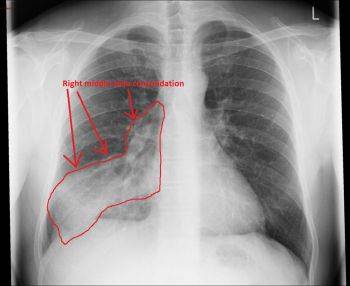

. عکس با اشعه ایکس برای دیدن محل و میزان گسترش التهاب در ریهها